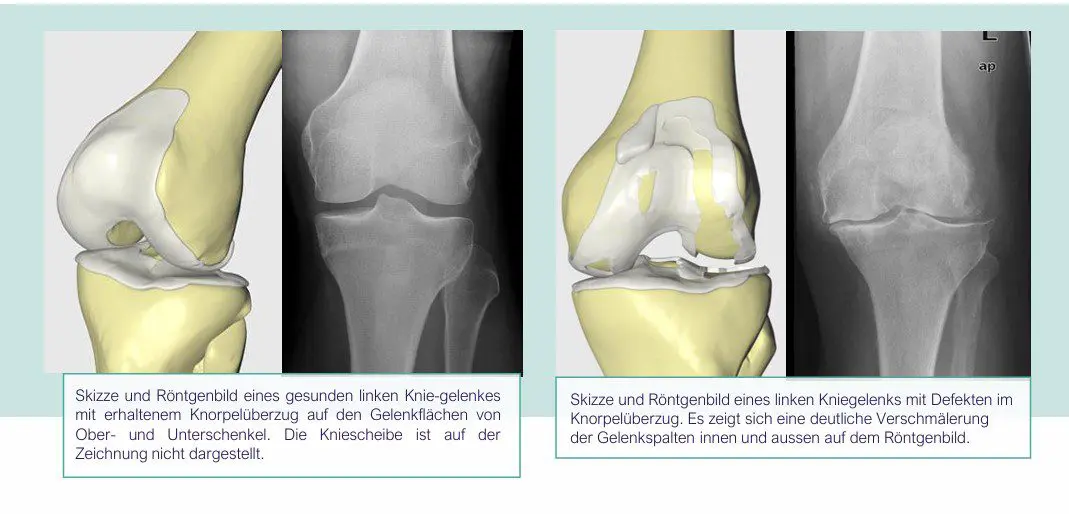

Zur Diagnose der Arthrose sind der Krankheitsverlauf, die klinische Untersuchung und ein Röntgenbild entscheidend. Im Röntgenbild zeigt sich der Knorpelverschleiss durch die Verschmälerung des Gelenkspalts. Die Aufnahmen werden unter Belastung des Gelenks im Stehen gemacht, zusätzlich wird die gesamte Beinachse untersucht. Bei Bedarf können „Stressaufnahmen“ zur Beurteilung der Bandstabilität und des Kniezustands angefertigt werden.